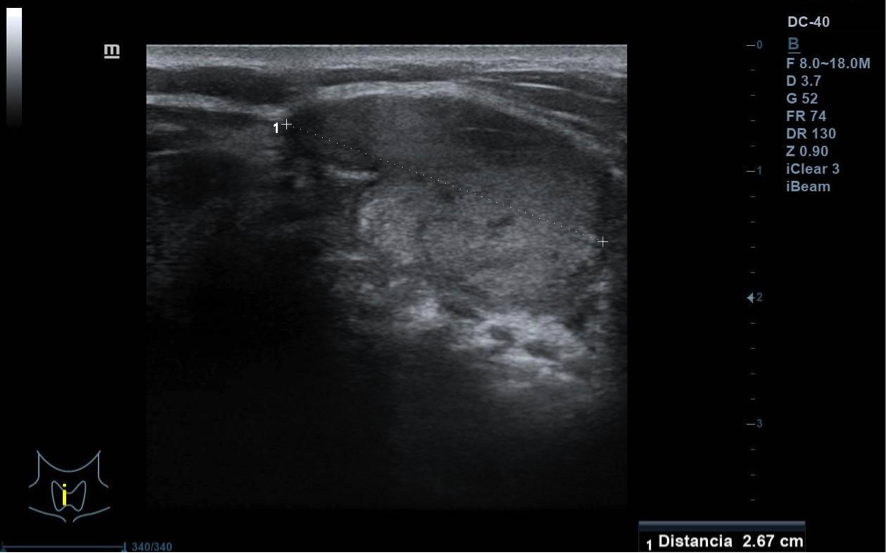

Se visualiza nódulo tiroideo en la unión del istmo con lóbulo tiroideo derecho, sólido, con cierta heterogenicidad, halo grueso anecogénico. Una zona del borde irregular, con mayor señal Doppler y de crecimiento excéntrico. Mide de diámetro máximo 25 x 20 mm. Adenopatías no patológicas.

La paciente fue remitida a Endocrinología para valoración de nódulo tiroideo de 2,5 cm, se solicitó ecografía para PAAF que objetivó nódulo TIRADS-4, PAAF con categoría Bethesda IV: neoplasia folicular con signos de células de Hürtle. Técnica IHQ de Calcitonina negativa. Se envía a Cirugía general y Digestivo para programar cirugía. Se realiza istmectomía y la AP revela que se trata de un tumor folicular de potencial maligno incierto, márgenes libres. Estudio genético con mutación del gen TERT.